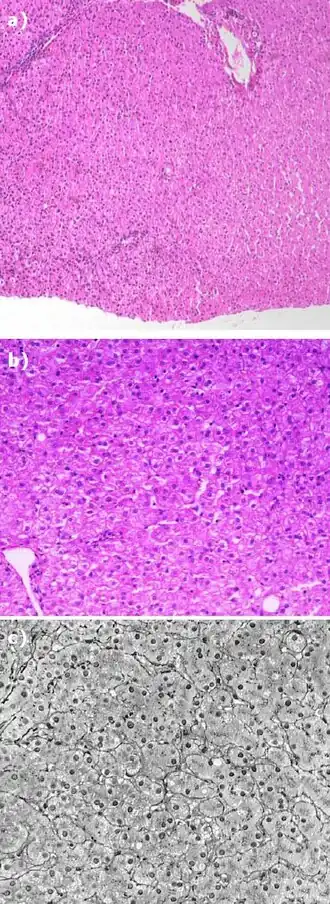

Martwica centralnozrazikowa wątroby człowieka w preparacie barwionym hematoksyliną i eozyną – w środku zdjęcia widać uszkodzone komórki, utratę prawidłowej struktury tkanki oraz krwinkotoki i skąpe nacieki zapalne w otoczeniu pól martwicy.

Komórki tkanki wątroby człowieka wybarwione: a) hematoksyliną i eozyną, b) w reakcji PAS, c) solami srebra